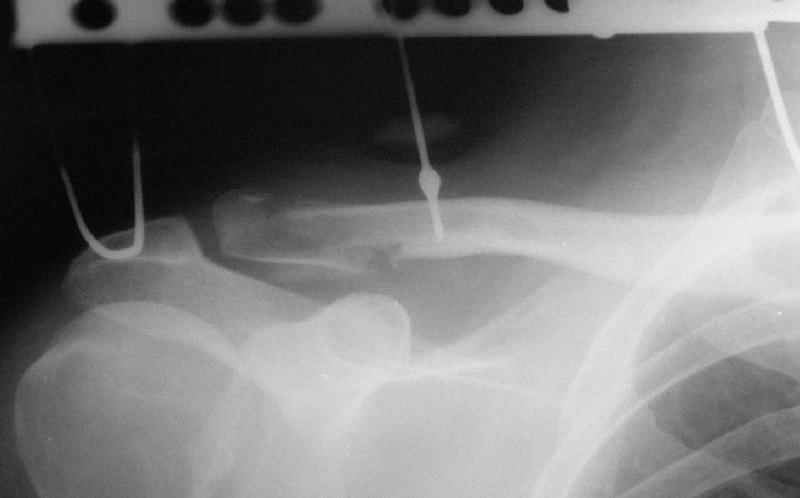

Re: Несросшийся перелом ключицы

При данных повреждениях возможно применение как АВФ, так и открытые способы лечения. Выбор в основном определяется давностью травмы, требованиями больного и отношением хирурга к тому-или иному способу лечения. В данном случае, учитывая смещение фрагмента с прикреплением кл-кл связки каудально, необходимо было "утопить" проксимальный отломок, что и сделано АВФ.